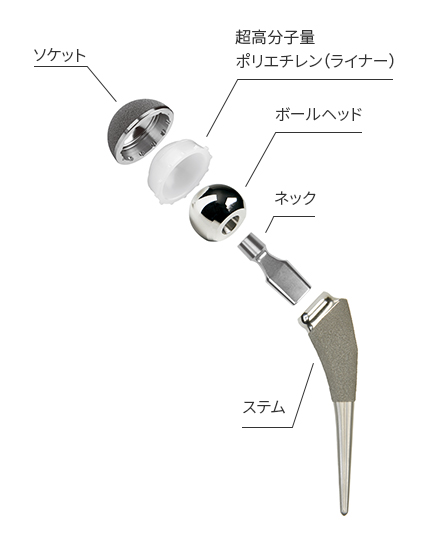

人工股関節置換術−MISから再置換まで応用できる手技のコツ [DVD付] (OS NOW Instruction) | 岩本 幸英 |本 | 通販 | Amazon, コラム27 人工関節メーカーに伺いました|人工関節コラム|人工関節とは|人工関節ドットコム,

コラム27 人工関節メーカーに伺いました|人工関節コラム|人工関節とは|人工関節ドットコム, 人工股関節置換術と人工骨頭置換術 | 世田谷人工関節・脊椎クリニック,

人工股関節置換術と人工骨頭置換術 | 世田谷人工関節・脊椎クリニック, 人工股関節置換術 MIS について | 人工関節について|湘南鎌倉人工関節センター|人工股関節置換術に特化,